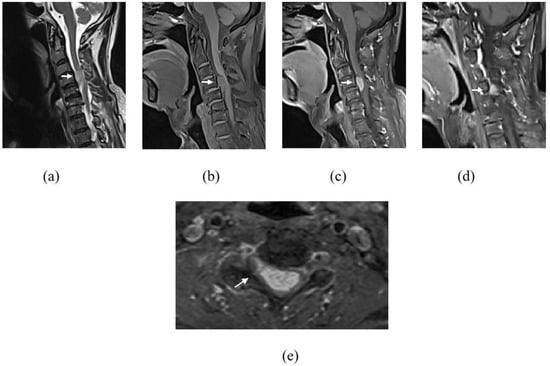

Figure 3.

Sagittal images (a–d) at T8 to T10 level showing lesion (white arrow) at T9 vertebral body demonstrating hyperintense signal on T1WI (a) and T2WI (b) with signal suppression on fat saturation sequence (c) and minimal enhancement on post contrast sequence (d), typical of hemangioma. Coronal bone algorithm CT shows classic corduroy sign in hemangioma at T9 vertebral body (e). Sagittal plane of thoracolumbar spine (f) of 18F-FDG PET/CT also showed reduced FDG metabolism of the T9 lesion (white arrow) with no FDG avid lesion seen at the thoracolumbar spine to suggest metastasis. Another small lesion (arrowhead) at T10 vertebral body which is isointense on T1WI (a), hyperintense on T2WI (b) with enhancement on post contrast sequence (d).